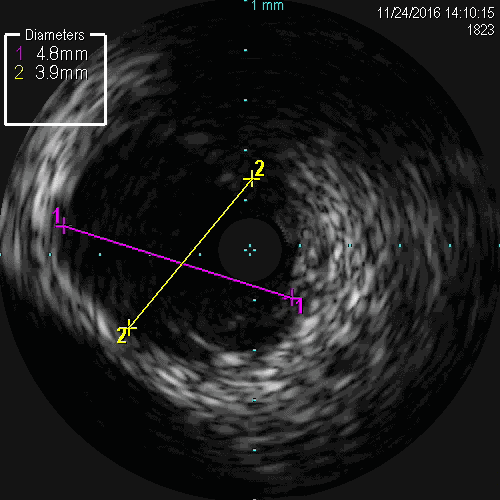

LCX-IVUS

LCX远端真腔,近端内膜下

IVUS结果